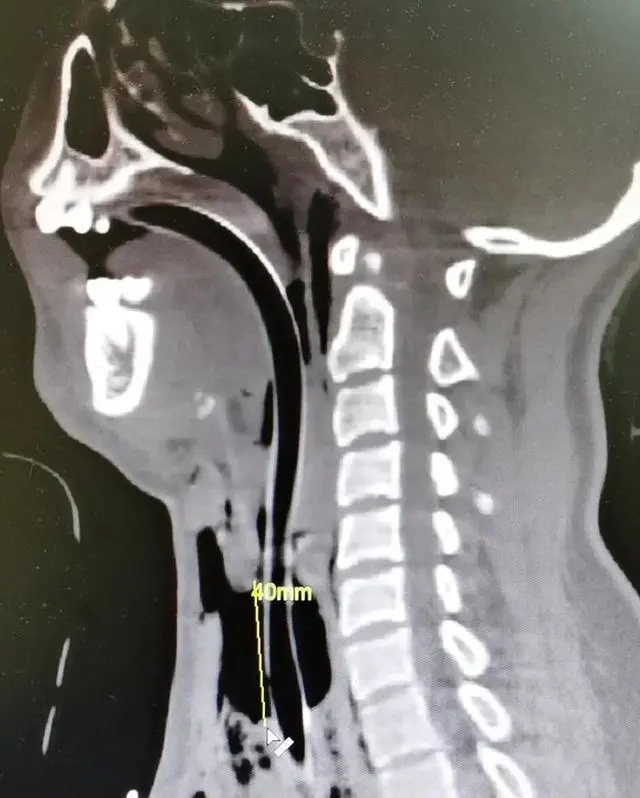

气管割出最长4厘米缺口

浙大二院急诊医学科副主任医师谢天舜说,小郭被送进来的时候,脖子上有红色的勒痕,腿上有大片外伤,呼吸困难,喉咙非常疼痛,并伴随有血痰吐出。

“我们考虑,应该是被勒了以后引起的颈部损伤,有可能有血肿、水肿,所以说后来考虑到安全问题就给她气管插管,但是插管的过程中发现气管破了,最长的缺口有4厘米。

当天,小郭就做了长达5个小时的手术。“气管切开之后对缺口进行了处理,现在还有一个气管套套在这里。刚刚手术,有可能还会引起一些感染的并发症,像肺部的感染等等,这些后续的感染需要预防。”谢天舜说。